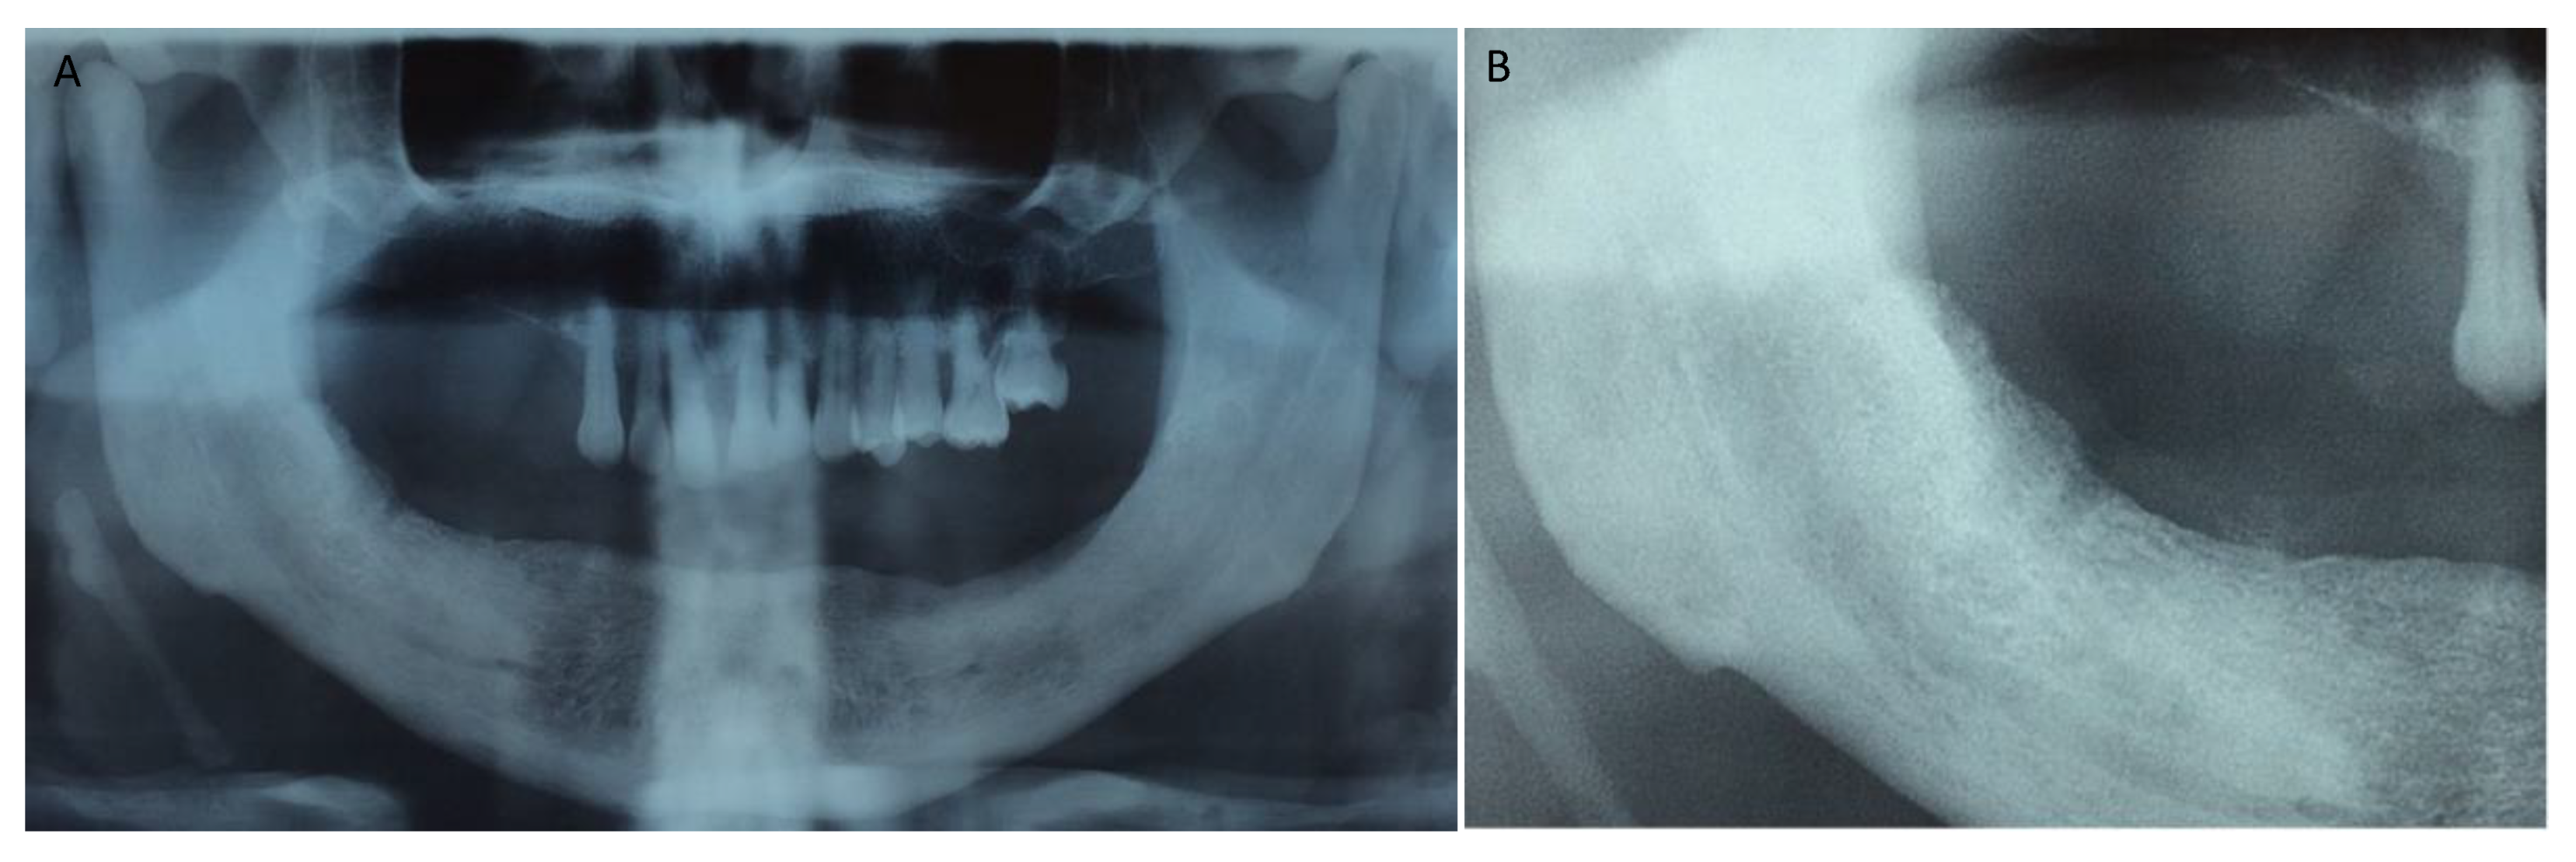

Figure 1, Figure 2, Figure 3, Figure 4, Figure 5, Figure 6 and Figure 7 show the progress of treatment in one of the patients of the test group. In Figure 3 reduction of the medullar space is visible, that may create a chronic ischemic area susceptible to necrosis.

Figure 6.

(A,B) Post-operative intra-oral view at 2 week follow-up. Mucosal healing without bone exposure can be seen.

Figure 7.

(A,B) Post-operative intra-oral and radiographic view at 6 month follow-up showing healed soft (A) and hard (B) tissues.